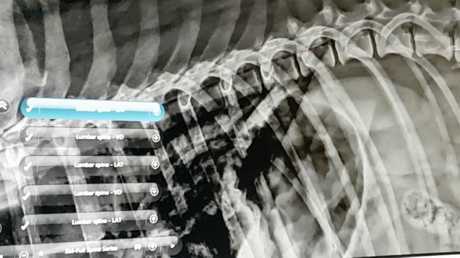

Interesting radiographs of a dog's secret past

Play this video

05 Mar 2017

(Duration 03:05)